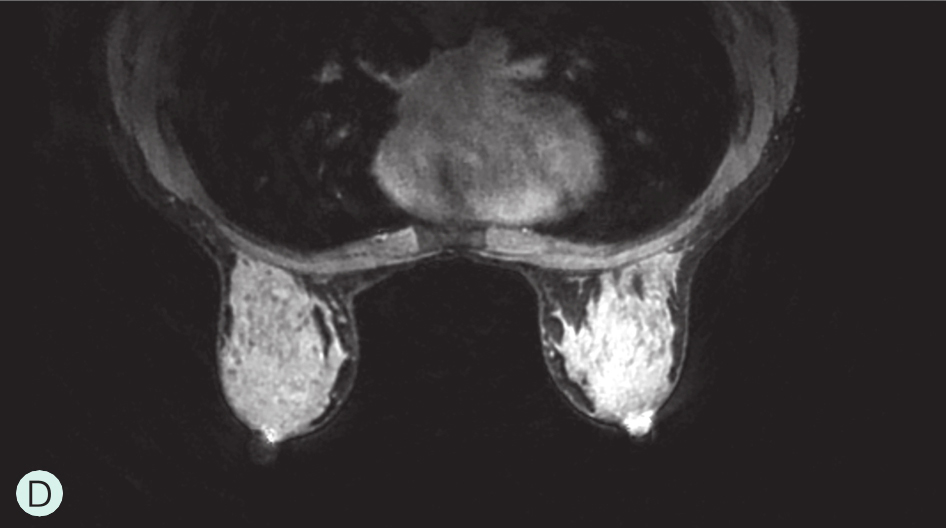

D级:极度致密型(降低乳腺钼靶摄影的敏感性)(图1-3-1D、图1-3-2D、图1-3-3D)。

图1-3-3 乳腺MRI不同乳腺密度

A.脂肪型;B.散在致密型;C.不均匀致密型;D.极度致密型